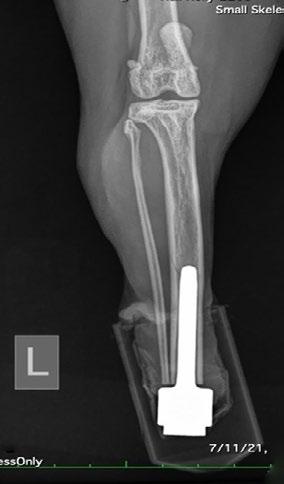

Osseointegrated Transcutaneous Amputation Prostheses in Veterinary Medicine

Daniel R James